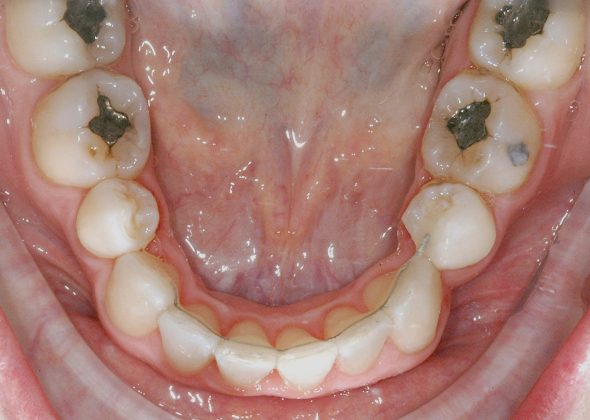

Al termine del trattamento ortodontico, che ha richiesto 24 mesi di terapia, è stata applicata una contenzione fissa3 all’arcata inferiore mediante filo multi-intrecciato coassiale .0195” esteso da 4.4 a 3.5 al fine non solo di stabilizzare il risultato sia sul piano orizzontale sia verticale, ma soprattutto per prevenire adeguatamente l’affollamento dentale terziario (Figure 9a-e).

All’arcata superiore è stato mantenuto il pontic in composito in sede 1.2, poiché la paziente, per esigenze personali, aveva preferito rimandare a un tempo successivo la sostituzione implantare di 1.2 agenesico, così come la coronoplastica definitiva di 2.3.

Dopo tre anni dal termine del trattamento ortodontico, la paziente ha richiesto di finalizzare il suo caso; è dunque stata effettuata la sostituzione implanto-protesica dell’elemento 1.2, senza necessità di ulteriori rifiniture ortodontiche, avendo mantenuto, grazie al pontic in composito, un ottimo parallelismo radicolare tra 1.1 e 1.3.

È stata eseguita contestuale terapia rigenerativa, per ottimizzare qualità e quantità dei tessuti nel sito implantare. Come si rileva dalle immagini di follow up, dopo la fase implanto-protesica superiore, è stata applicata anche una parziale contenzione fissa tra gli incisivi centrali superiori e il risultato ortodontico si è mantenuto stabile nel tempo (Figure 10 a-e).